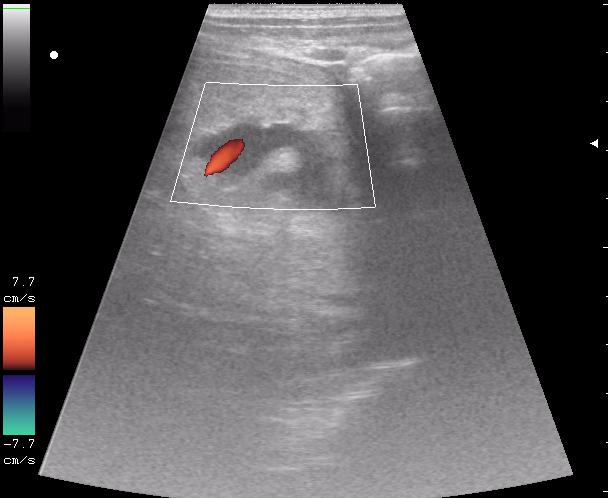

конец рабочего дня тоже "порадовал". Травма об руль велосипеда.

По поводу "разможжения" ткани паренхиматозного органа при травме. Скорее всего-это участки попитывания кровью,т.н. имбибиция.